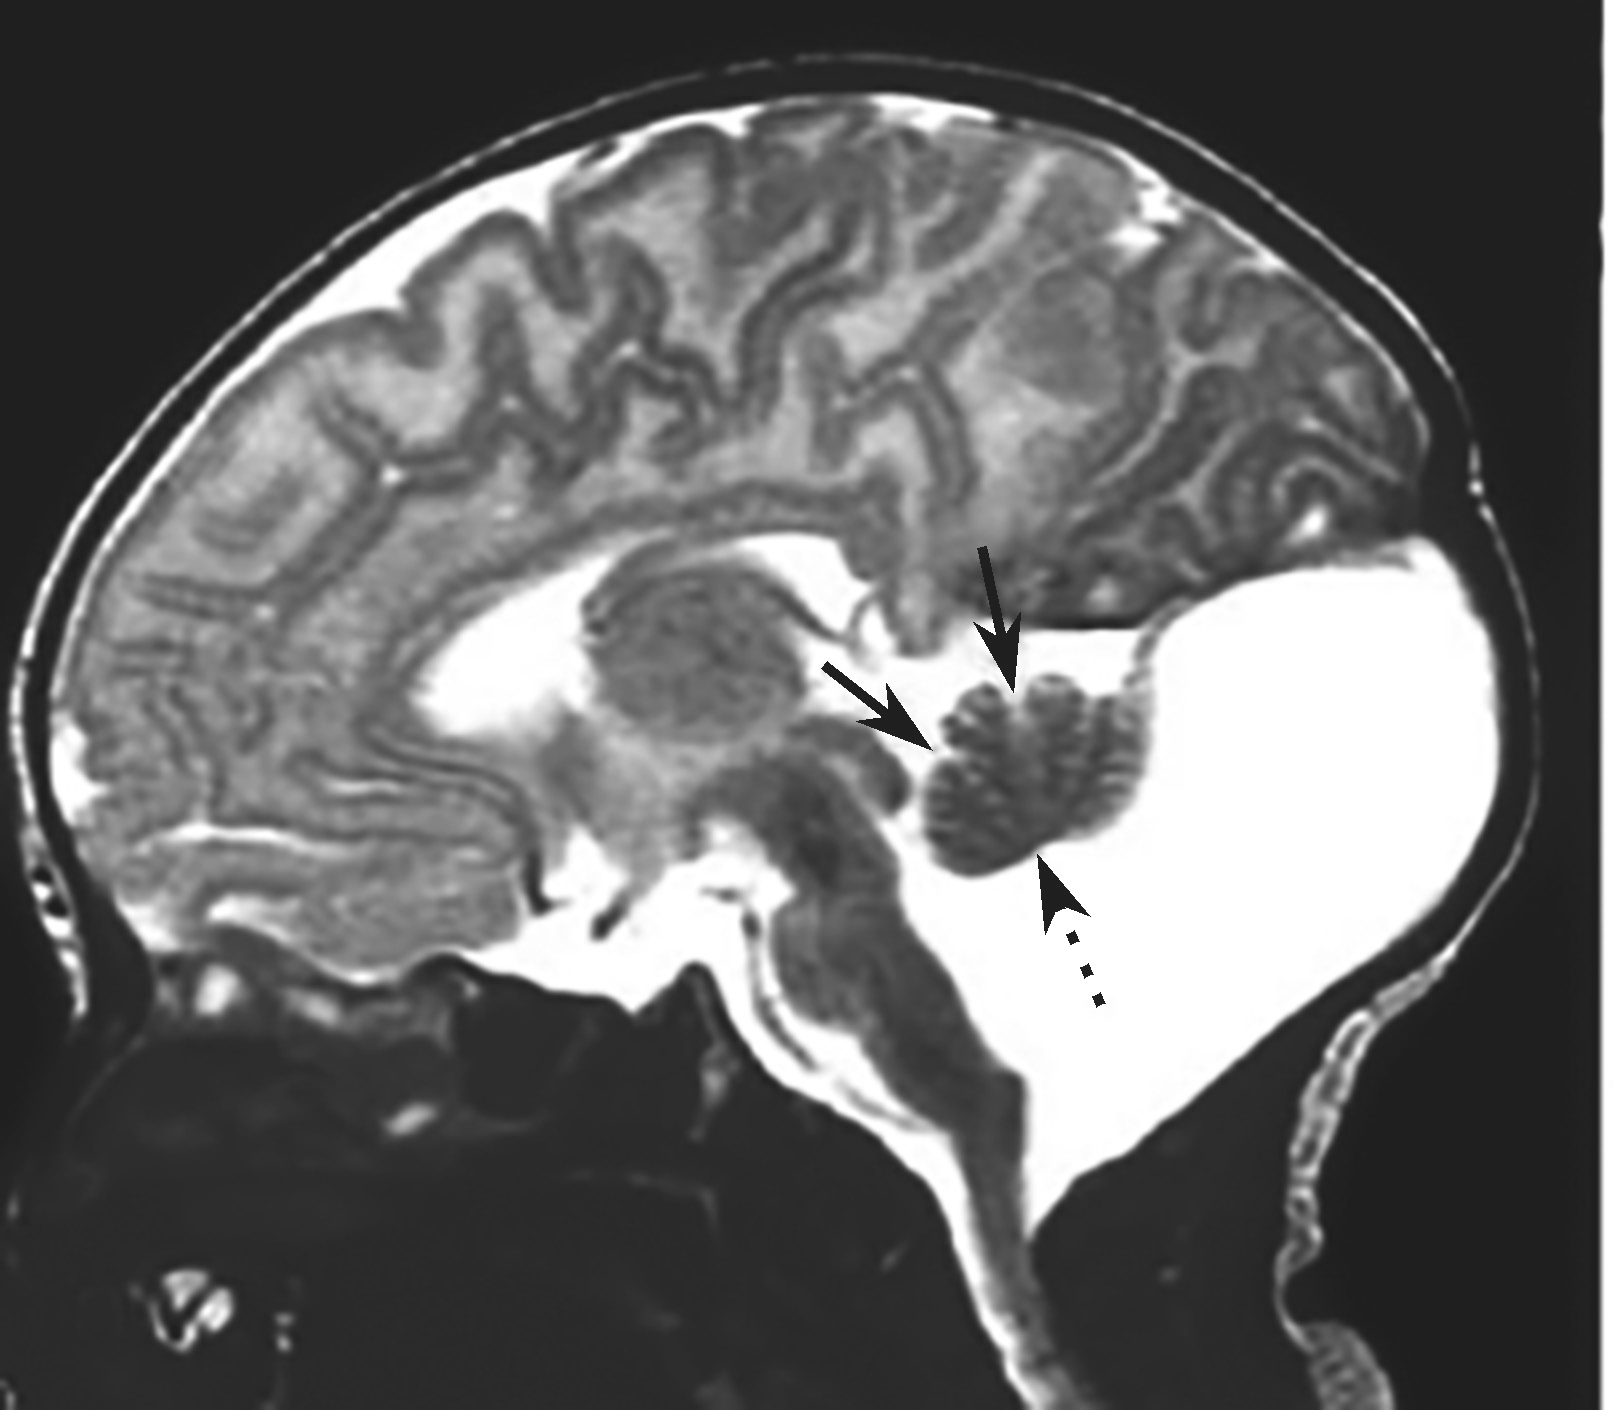

(2)MRI是诊断本病最可靠的方法,其特征表现为:

①颅后窝极度增大,伴横窦及窦汇抬高,超过人字缝;②天幕上抬超过人字缝,在冠状位和矢状位上显示尤清;③巨大的囊肿占据了颅后窝中线的绝大部分,并与扩大的第四脑室相通;④常伴有不同程度的脑积水,导水管扭结不通,小脑下蚓部缺如;⑤上蚓部被扩大的第四脑室及后方的囊腔推挤向前上方移位(图4-1-3)。需借助MRI与Blake囊肿、巨脑池、蛛网膜囊肿、单纯蚓部及小脑发育不全鉴别。

图4-1-3 患儿上蚓部向前上方移位

辅助检查:头颅MRI(图4-1-4)检查示双侧脑室系统对称性显著扩大,脑室前、后角变钝,双侧大脑半球脑实质明显变薄,脑实质内未见明确异常信号,颅后窝枕大池扩大,双侧小脑半球受压、上抬,小脑幕抬高,小脑蚓部缺如。

图4-1-4 头颅MRI检查